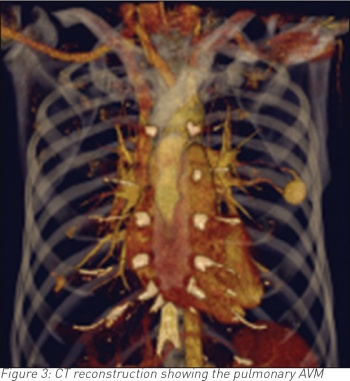

A 35-year-old male, who is otherwise fit and healthy, presented with a 10-day history of cough and temperature. Bloods showed raised white cell count otherwise normal. Chest infection was suspected and a chest radiograph was requested. The latter showed a well-rounded soft tissue opacity in the left midzone with possibly a connecting vessel radiating to the hilum. Two smaller opacities were identified in the right lung. A computed tomography (CT) pulmonary angiogram with intravenous contrast followed and that confirmed the diagnosis of a PAVM of 2cm in the left upper lobe and exquisitely demonstrated the feeding artery and vein with further smaller PVMs of 1cm in the right lung. The patient declined any further intervention.

CT is often the diagnostic modality of choice.3 It differentiates PAVMs from other causes of pulmonary nodules or masses. On CT, the characteristic presentation of a PAVM is a homogenous non-calcified nodule up to several centimetres in diameter or a serpiginous mass connected with blood vessels. Occasionally associated phleboliths may be seen as calcification. Contrast injection shows enhancement of the feeding artery, aneurysmal part and the draining vein.3